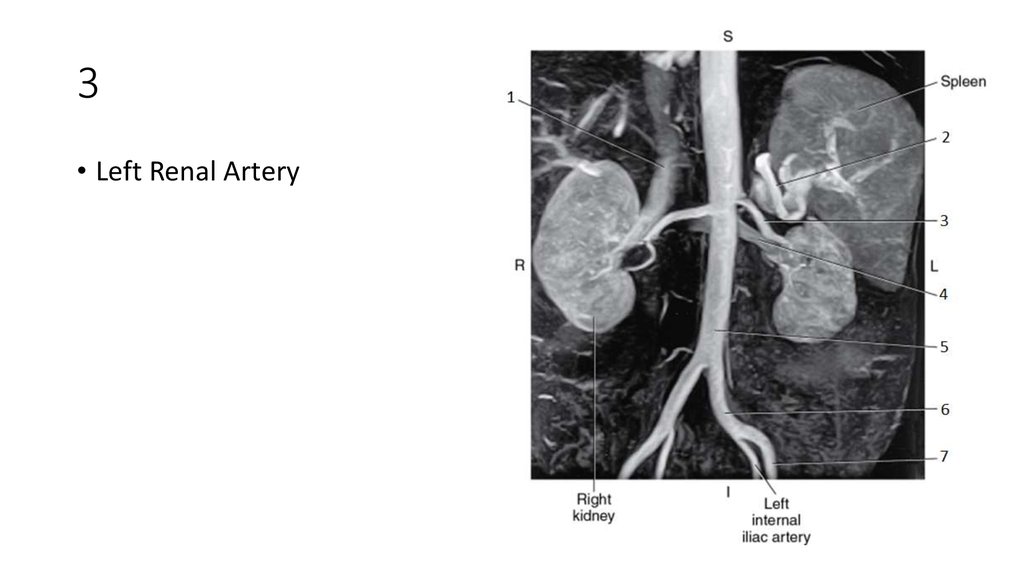

66. 3

67. 3

• Left Renal Artery